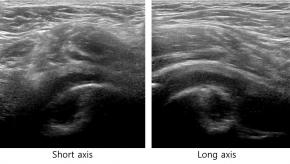

Elastography for the differential diagnosis of malignant versus benign testicular lesions: a meta-analysis

Ziwei Lin, Rui Lin, Huaiyu Wu, Linghu Wu, Jieying Zeng, Jinfeng Xu, Fajin Dong